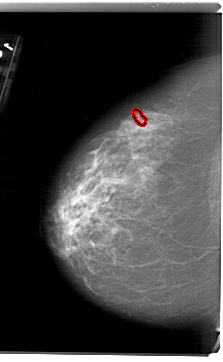

A_1626_1.LEFT_CC

LEFT_CC LINES 6871 PIXELS_PER_LINE 4231 BITS_PER_PIXEL 12 RESOLUTION 43.5 OVERLAY

FILE: A_1626_1.LEFT_CC.OVERLAY

TOTAL_ABNORMALITIES 1

ABNORMALITY 1

LESION_TYPE CALCIFICATION TYPE PLEOMORPHIC DISTRIBUTION CLUSTERED

ASSESSMENT 4

SUBTLETY 2

PATHOLOGY MALIGNANT

TOTAL_OUTLINES 1